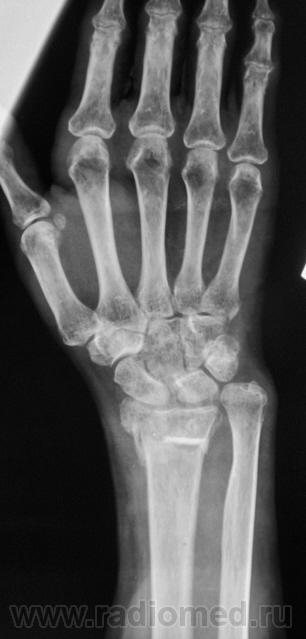

Фрагменты с увеличением.

Пусть интересуется... Гипс снят рановато, стояние отломков - неудовлетворительно,хотя бывает и хуже

Если срок сращения 4 недели, то признаки консолидации выражены соответственно сроку достаточно хорошо. Перелом компрессионный, поэтому произошел вывих в л/л суставе. Можно или нет его было устранить в амбулаторных условиях - судить не берусь. Осколок кортикала в луче "захряснет", может, рассосется - ничего страшного.

неприятная ситуация(особенно если не было первичной репозиции) есть оппределенные правила ведения таких переломов, первичный снимок, сразу после репозиции, через 4-5 дней после репозиции и если нет вторичного смещения в гипсе то через 4-5 недель уже без гипса. ситуация на данный момент спорная, лучше наложить аппарат Илизарова для дальнейшей иммобилизации и профилактики контрактуры л\зап сустава. если возраст пациентки почтенный, то гипсовая иммобилизация доолжна быть продлена до 8 недель.